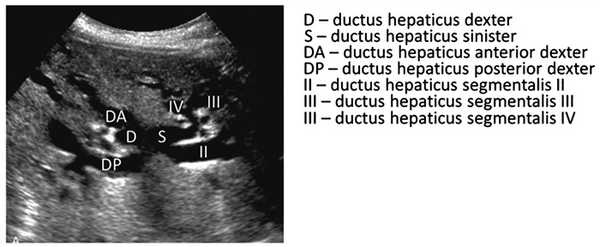

У здорового человека внутрипеченочные протоки ductus hepaticus dexter (правый печеночный проток) и ductus hepaticus sinister (левый печеночный проток) (рис. 1) не видны при ультразвуковом исследовании, виден при хорошей визуализации только ductus hepaticus communis (общий печеночный проток). Он соединяется с ductus cysticus (пузырный проток) и образуется ductus choledochus (общий желчный проток), который в норме имеет длину 5—7 см [4].

Рис. 1. Желчный пузырь и желчевыводящие пути.

Желчные протоки. На рис. 3 хорошо видны правый и левый печеночные и впадающие в них протоки, так как они расширены в результате обструкции желчных путей дистальнее за переделами печени (в норме не определяются) [9, 10].

Рис. 3. Внутрипеченочные желчные протоки (выявляются на фоне обструкции общего желчного протока).